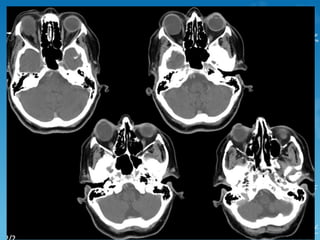

seven-year-old male patient with pulsatile tinnitus

Aberrant internal carotid artery

Some authors suggest that the reason could be the absence of the

hypotympanic bony plate because of a congenital failure of ossification.

With age, as the artery elongates and becomes tortuous, it protrudes

through the defect into the tympanic cavity.

Others suggest that the cervical ICA never develops and an aberrant carotid

artery forms when the inferior tympanic artery (a branch of the ascending

pharyngeal artery) enlarges to supply the territory of a cervical carotid

artery. The inferior tympanic artery runs through the middle ear and then

joins the horizontal petrous carotid artery. The so-called aberrant carotid

artery is, in fact, the markedly hypertrophied inferior tympanic artery.